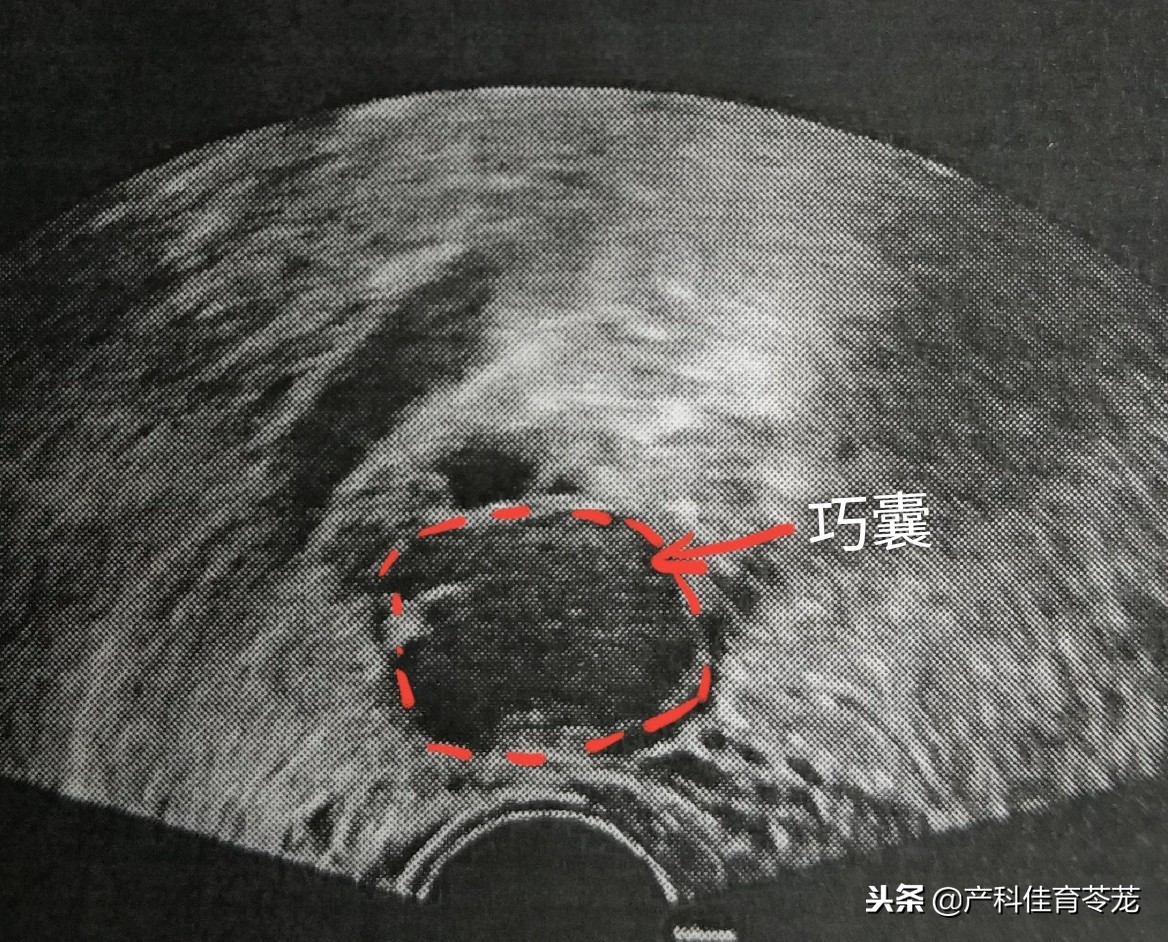

1、卵巢巧克力囊肿(内膜异位囊肿)

子宫内膜组织异位于卵巢,这些异位灶反复出血形成囊肿,里面是暗褐色粘糊状陈旧性血液,像巧克力,故又称为巧克力囊肿

这种囊肿B超诊断准确率很高:

同样里面是液体,但B超下看到的不是透亮的,里面有密集的细点状回声,说明不是单纯的一包“水”,而是有血。

巧克力囊肿的女性多数有痛经的症状,严重的会引起不孕,如果发生破裂会引起突发腹痛。